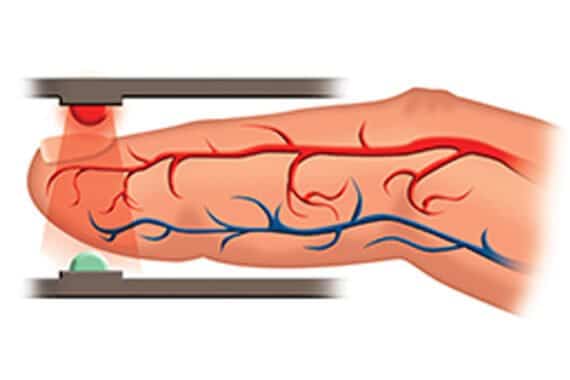

Nemi fyrir súrefnismettun – einnota fullorðins

- Easy to Use Illustrated finger guide ensures easy and accurate placement by caregiver or patient